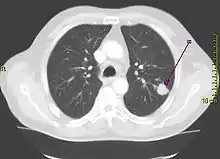

A radiografia de tórax é um dos primeiros métodos investigativos quando um paciente relata sintomas que sugerem um câncer de pulmão. Ela pode revelar uma massa óbvia, alargamento do mediastino (sugestivo de acometimento de linfonodos locais), atelectasia (colapso do alvéolo), consolidação (pneumonia) e derrame pleural.[1] A tomografia computadorizada (TC) é tipicamente utilizada para fornecer mais informações sobre o tipo e a extensão da doença. A broncoscopia ou a biópsia guiada por TC são frequentemente usadas para coletar amostras do tumor para análise histopatológica.[9]